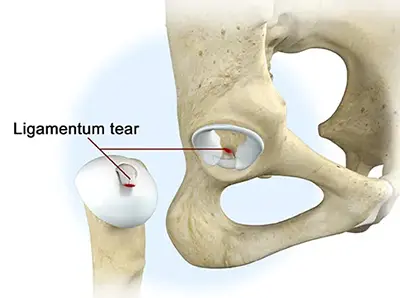

Ligamentum Teres Tears

What is a Ligamentum Teres Tear?

The ligamentum teres (LT) is a cord-like structure that connects the hip socket (acetabulum) to the femoral head (ball of the hip). It helps stabilize the hip joint. When the LT is torn, patients may feel hip instability, experience “giving out” of the hip, or have pain during movement.